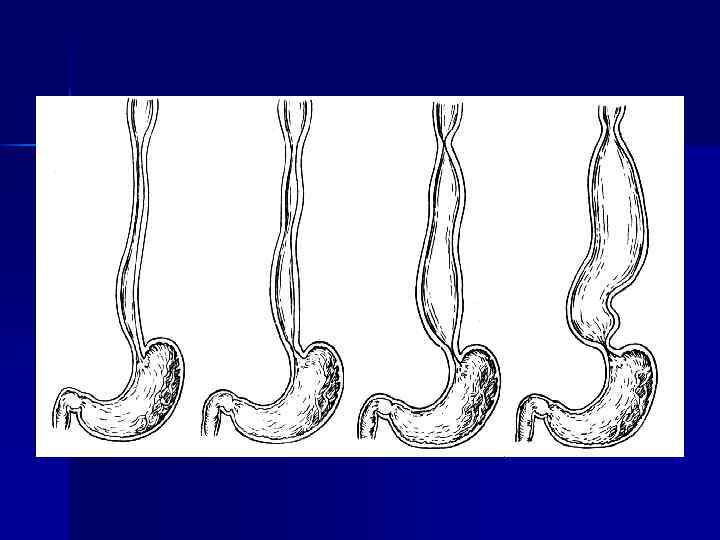

Рентгенологическое исследование: I стадия — компенсации (несколько расширенный желудок, усиление его перистальтики. Полная эвакуация контрастной массы из желудка замедлена на срок до 6— 12 ч) n n II стадия — субкомпенсации (желудок расширен, натощак содержит жидкость, перистальтика его ослаблена. Эвакуация содержимого происходит через 24 ч и позже) n III стадия — декомпенсации (желудок резко растянут, натощак в нем большое количество содержимого. Перистальтика резко ослаблена. Эвакуация контрастной массы из желудка задержана более чем на 24 ч)